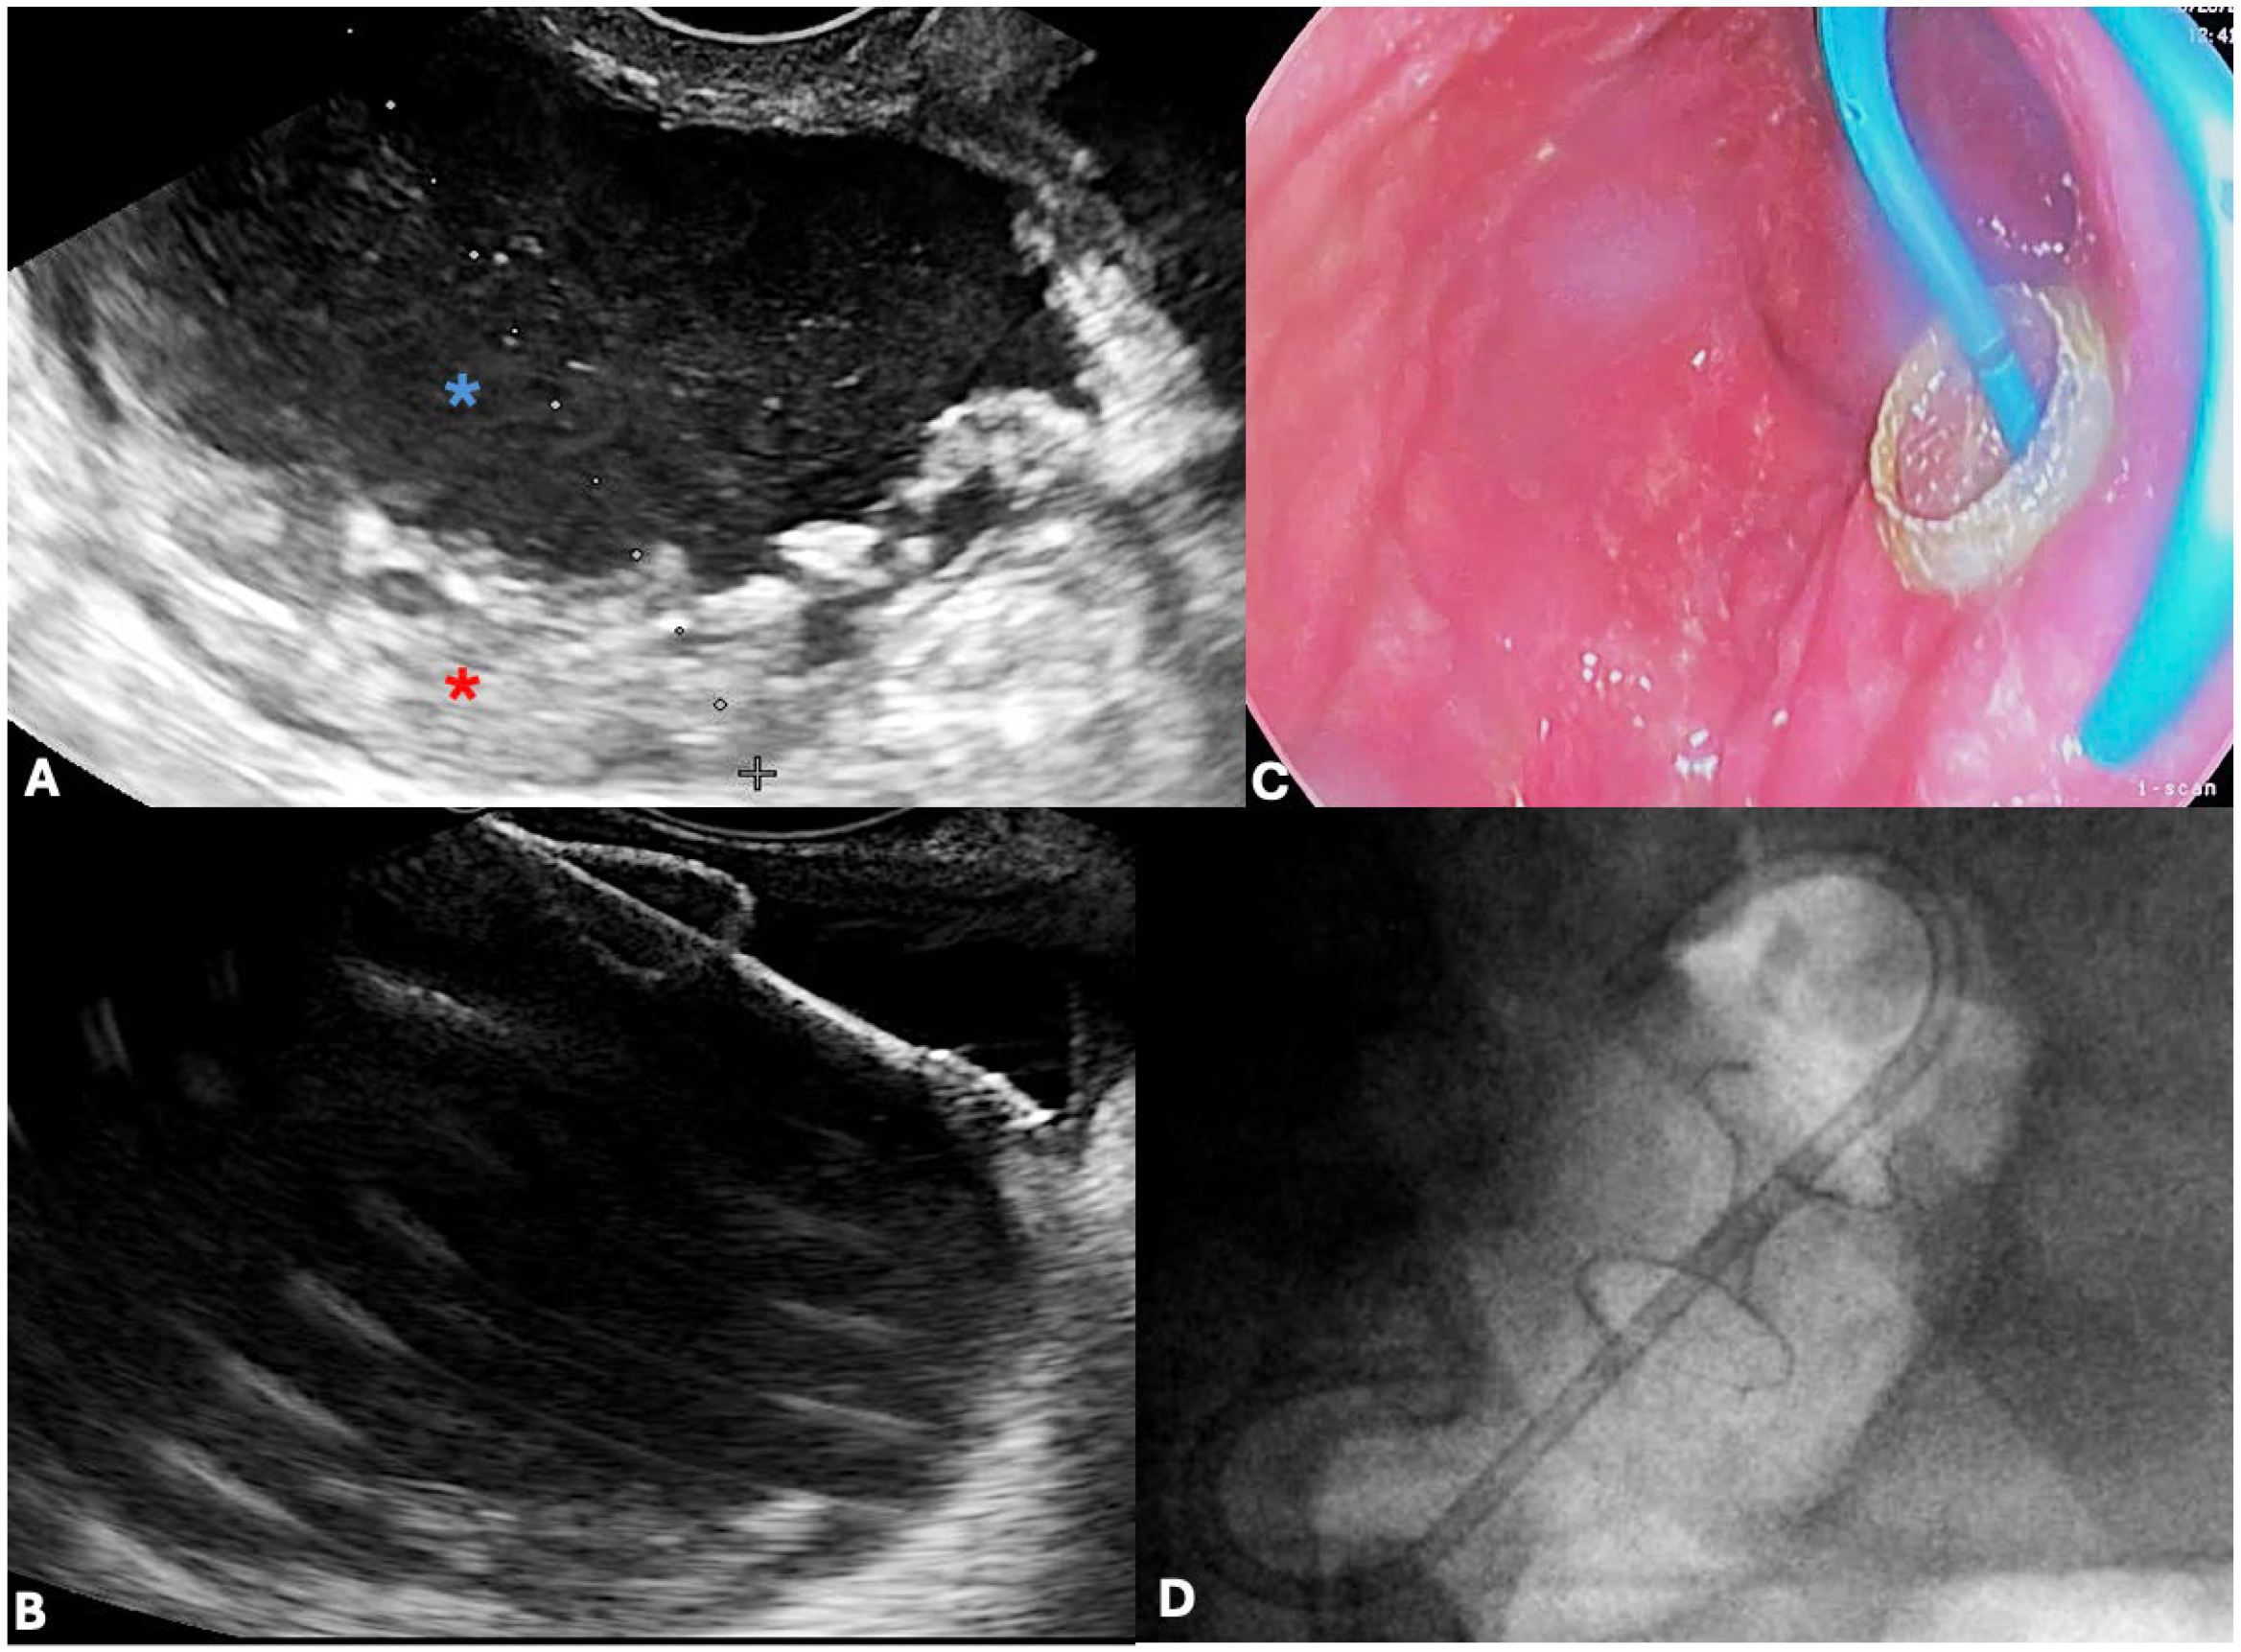

5.2.1. EUS-Guided Transmural Drainage

5.2.3. Endoscopic Necrosectomy for WON

Direct Endoscopic Necrosectomy (DEN) Techniques